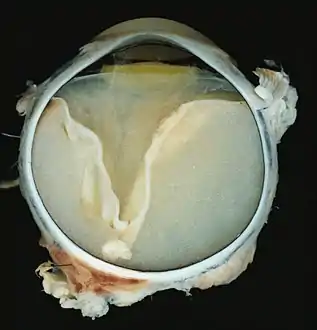

A case of Coats' disease, showing total retinal detachment with subretinal exudate containing cholesterol crystals and a fibrous nodule in the posterior pole

Grossly, retinal detachment and yellowish subretinal exudate containing cholesterol crystals are commonly seen. Microscopically, the wall of retinal vessels may be thickened in some cases, while in other cases the wall may be thinned with irregular dilatation of the lumen.[10] The subretinal exudate consists of cholesterol crystals, macrophages laden with cholesterol and pigment, erythrocytes, and hemosiderin.[11] A granulomatous reaction, induced by the exudate, may be seen with the retina.[12] Portions of the retina may develop gliosis as a response to injury.